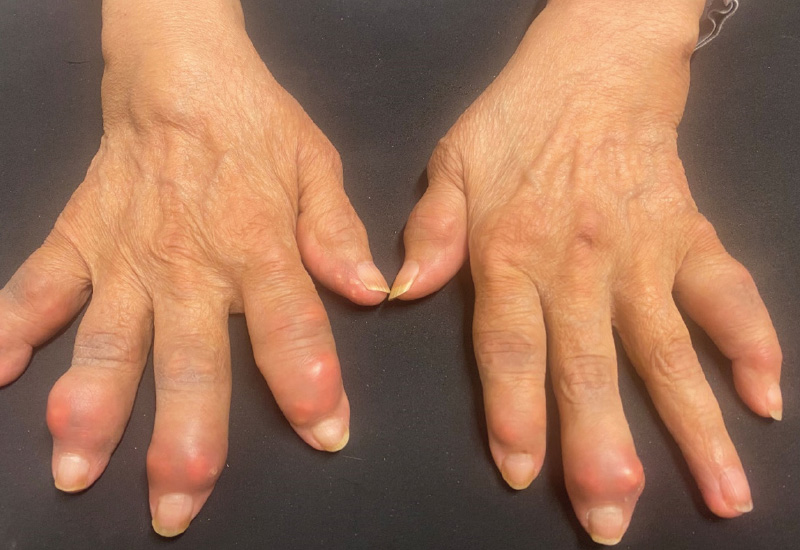

KLINISCHER BEFUND: 165 cm, 75 kg. Gelenkstatus: Verdickungen, Hautrötung, Überwärmung und z. T. Ablagerungen in den Fingergelenken beider Hände (Abb. 1).

DIAGNOSE: Destruierende, tophöse Arthritis urica